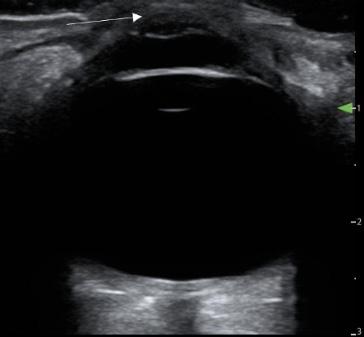

Onphysicalexamination,thepatienthadanoral temperatureof99° Fahrenheit(37.2° Celsius),tachycardiaof 108beatsperminute,bloodpressureof106/71millimetersof mercury,97%oxygensaturationonroomair,andadiffusely tenderabdomenwithvoluntaryguardingandrebound tendernesssuggestiveofperitonitis.APOCUSwas performedtoassessforintraperitonealfree fluid.Itrevealeda complexcollectionof fluidwithinternalechoesinthe hepatorenalspaceraisingconcernforaloculatedinfection (See Image and Video).

Abdomino-pelvicPOCUSmayguidetriage,diagnosis, andmanagement,assistingtheclinicianininvestigatinga rangeofdiseaseentitiesincludingbiliarypathology, abdominalaorticaneurysm,orTOA.3–5 Bedsideultrasound isgenerallyreadilyavailableintheEDsettingandmayserve asanadditionalmodalitytoidentifyunusual findingsearlyin thepatient’sclinicalcourse.Itdoesnotrequireionizing radiationandisnottimeintensivetoperform.Cliniciansmay considerearlyuseofPOCUSforperitoneal findings,as evidencedinthiscasepresentation.Inconjunctionwith informationobtainedonhistoryandphysicalexamination, theunusual,rightupperquadrantPOCUS findingsof intraperitoneal fluidwithloculationscausedconcernfora disseminatedpelvicinfection.Thiswasconfirmedasa rupturedTOAwithamoderateamountofpurulent, intraperitonealfree fluidontheoperativereport.Fitz-HughCurtissyndromewasaconcerngiventhecomplicated fluidvisualizedwithPOCUS,buttherewasnocommentof violin-stringadhesions,adhesions,or fibrousadhesions betweentheanteriorhepaticcapsuleandparietal peritoneumnotedonthelaparoscopicoperativereport, althoughitisunknownwhetherthisanatomicarea wasevaluated.

Intraperitoneal fluidiseasilyvisualizedonultrasound, andwhencomplex fluidwithloculationsisencountered,the differentialdiagnosisincludesmalignancy,inflammation, andinfectiousprocesses.6 Similar findingsofseptated intraperitoneal fluidhavebeendocumentedincases of Ctrachomatis inPID,7 cholecystitis,8 and tubercularperitonitis.9

GroupAstreptococcusisararecauseofpelvic in fl ammatorydisease,usuallyseenintheperipartum period,inpatientswithanIUDorwhohavehadother recent,invasivegynecologicprocedures.Inapatientnot respondingtoantibioticsadministeredfortypicalPID coverage,GASshouldbeconsideredasapossibleetiology andapenicillin-basedantibioticadministeredtoprevent progressiontotubo-ovarianabscessformation,peritonitis, andsepsis,particularlyincasesofreturningpatients previouslytreatedwithantibiotics.Bedsideultrasound shouldbeperformedinpatientspresentingwithabdominal pain,anduncommon fi ndingsshouldtriggerfurther investigation.Toourknowledge,noothercasesofloculated fl uidinthehepatorenalspaceassociatedwithPIDhave beenreported.

Video. Rightupperquadrantultrasonographyusingcurvilinear probefanningthroughthecoronalplanedemonstratingascitesand septationsinapatientultimatelydiagnosedwithpelvic inflammatorydisease.